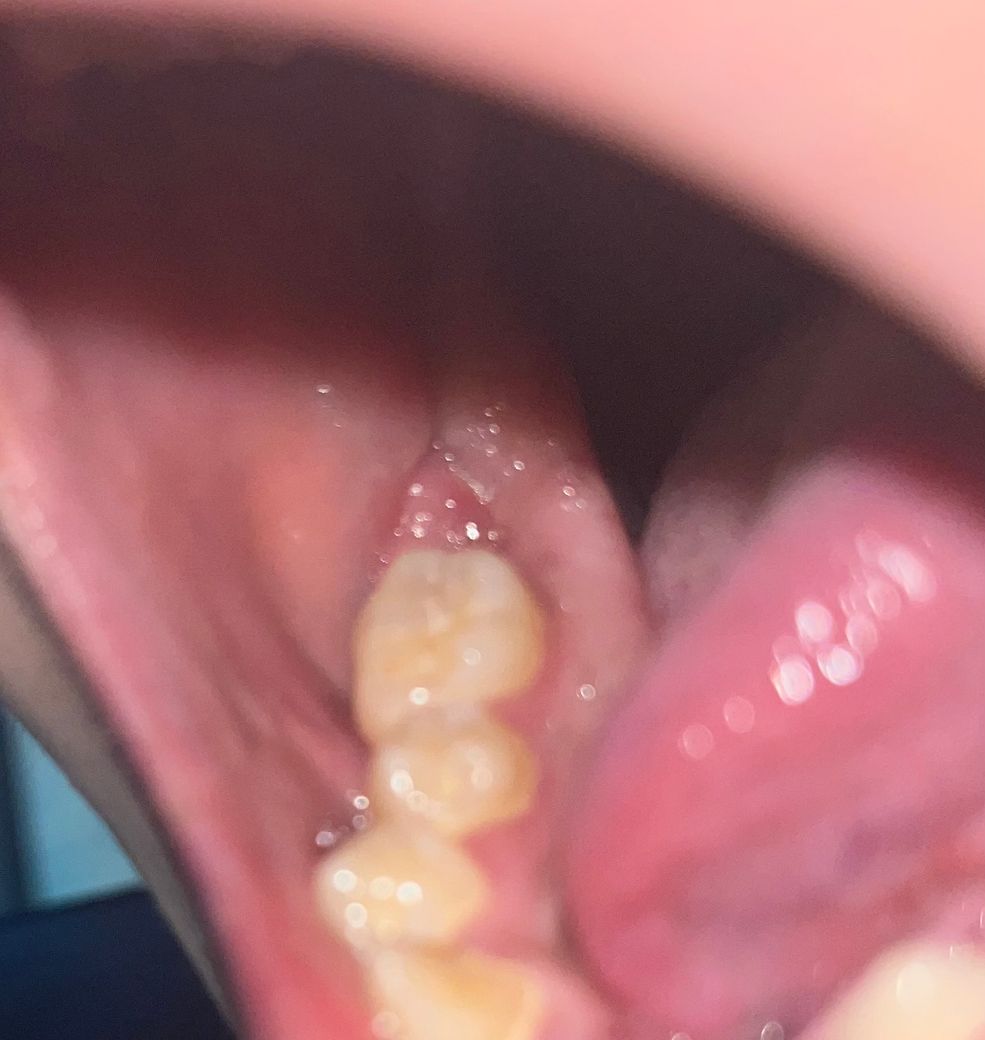

뼈이식 임플란트 실밥제거후 2주 지났는데 염증인가요?

뼈이식 임플란트 후에 실밥제거을 하고 나서 2주가 지났습니다 근데 오늘 아침부터 뭔가 조금 부은 느낌이 있어서 보았더니 조금 빨갛게 살짝 부어올라왔는데 염증이 생긴걸까요?

• 2번 째 사진

사진으로 보아서는 정확한 판단이 어렵지만 부었다면 치과를 방문하는 것이 좋습니다. 임플란트 주위에 염증이 있는 경우에 붓는 경우가 간혹 있습니다. 따라서 지체하지 마시고 임플란트를 시술한 치과를 방문하여 검사를 해보시길 바랍니다.

사진 상 눈에 띄는 염증 소견은 보이진 않습니다. 통증이 심해지거나 붓는다면 치과 가보시는 게 좋습니다.

사진상으로는 염증이 생긴것으로 보이지는 않습니다. 하지만 통증이 동반이 되는 경우에는 염증가능성이 높기에 치과 진료를 받길 권합니다.

잘 아물고 잇는거 같습니다. 염증이 있는건 아니니 걱정하지 마시고 관리를 잘해주시면될것같습니다.